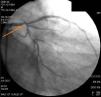

O doente foi submetido a coronariografia invasiva que confirmou doença coronária significativa (Figura 3) e foi referenciado para cirurgia de revascularização miocárdica. Os autores não tiveram acesso às imagens da primeira coronariografia porque foi realizada em outra instituição e por outro operador. O doente quando nos foi referenciado era portador apenas de uma informação clínica: acompanhar o pedido da AngioTC cardíaca.